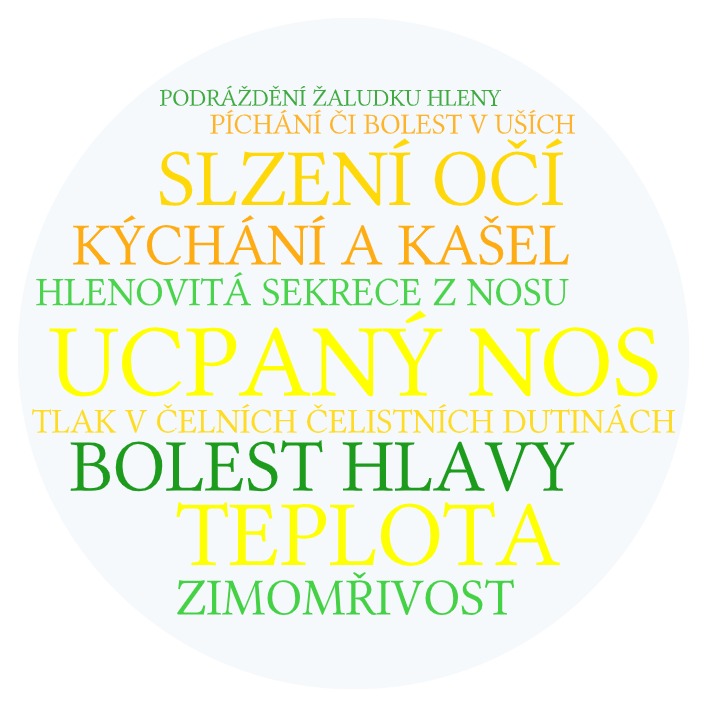

Běžná rýma je vodnatá či bělavě zabarvená. Její příčinou jsou nejčastěji viry a většinou při klasické léčbě odezní za 5 - 7 dní.

Vedle rýmy nás běžná virová onemocnění často potrápí tzv. nachlazením, tedy škrábáním či bolestí v krku, kašlem a zvýšenou teplotou. K tomuto účelu slouží běžné úlevové léky ve formě pastilek, sprejů, tablety, sirup nebo čípek na bolest hlavy a zvýšenou teplotu. Pokud jste fanoušky bylinných produktů a přemýšlíte, jak se rychle zbavit rýmy, můžete vyzkoušet třeba oblíbený DR. WEISS Rymastop bylinný nosní sprej 30 ml, který obsahuje 10 bylinných extraktů pro rychlou úlevu. Aby rýma netrvala moc dlouho, prospějí naší imunitě také vitamíny a minerály.

Běžná rýma je vodnatá či bělavě zabarvená. Její příčinou jsou nejčastěji viry a většinou při klasické léčbě odezní za 5 - 7 dní.

Vedle rýmy nás běžná virová onemocnění často potrápí tzv. nachlazením, tedy škrábáním či bolestí v krku, kašlem a zvýšenou teplotou. K tomuto účelu slouží běžné úlevové léky ve formě pastilek, sprejů, tablety, sirup nebo čípek na bolest hlavy a zvýšenou teplotu. Pokud jste fanoušky bylinných produktů a přemýšlíte, jak se rychle zbavit rýmy, můžete vyzkoušet třeba oblíbený DR. WEISS Rymastop bylinný nosní sprej 30 ml, který obsahuje 10 bylinných extraktů pro rychlou úlevu. Aby rýma netrvala moc dlouho, prospějí naší imunitě také vitamíny a minerály.